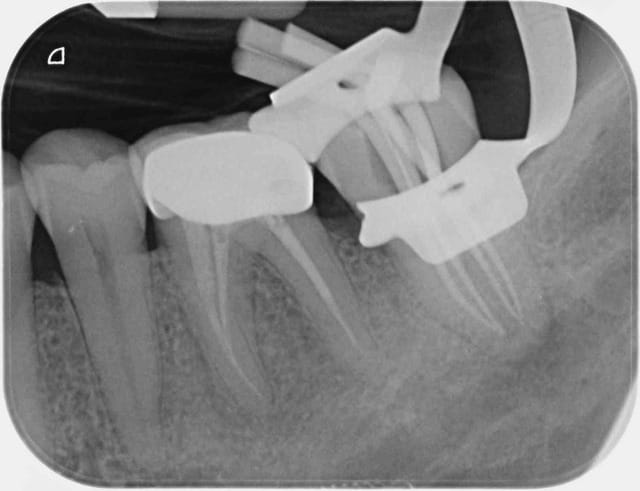

De plus, quand on utilise le QS, ce serait une erreur de le garder seulement pour les molaires mandibulaires. Voir la radio bite-wing de mon patient de ce matin pour le secteur 1: 1 carpule entre 16-17 et 1/2 entre 14-15 et j'ai pu soigner de 14 à 18. Aucune douleur lors de la réalisation de l'anesthésie, pas besoin "d'attendre que ça prenne", pas d'engourdissement de la joue, et anesthésie complète des dents + des tissus mous, ce qui est drôlement pratique pour passer les coins interdentaires lors de la pose des matrices.